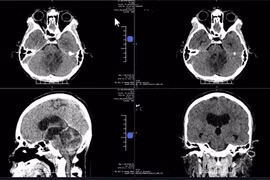

Liệt lưỡi do u não chèn ép thần kinh, bay từ Mỹ về Việt Nam giải cứu

Ứng dụng robot và hệ thống định vị, vi phẫu hiện đại giúp phẫu thuật các khối u não nằm ở vùng "nhạy cảm" hiệu quả.